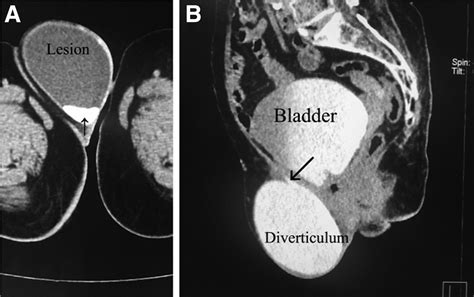

Diagnosing a Urinary Bladder Diverticulum requires imaging to visualize the bladder structure. Urologists typically utilize a combination of the following methods:

CT Urography Provides detailed images to rule out stones or tumors within the pouch.